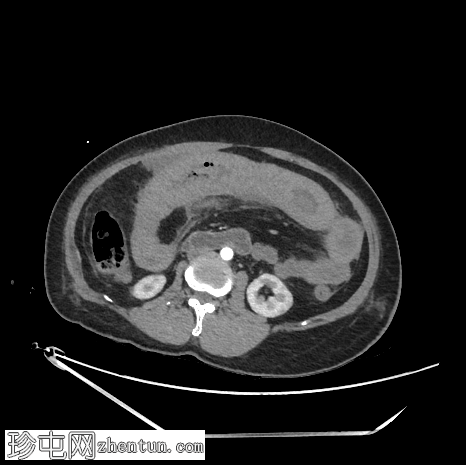

矢状位增强扫描

动脉期

空肠(长段,60 cm)肠壁弥漫性节段性增厚。肠壁呈高密度影,平扫CT值约为56 HU,并可见强化。

可见肠系膜水肿和血管充血,以及少量腹水。

肠系膜上动脉和静脉通畅,未见血栓。

影像学表现最提示黏膜下出血。

鉴别诊断包括感染性肠炎。